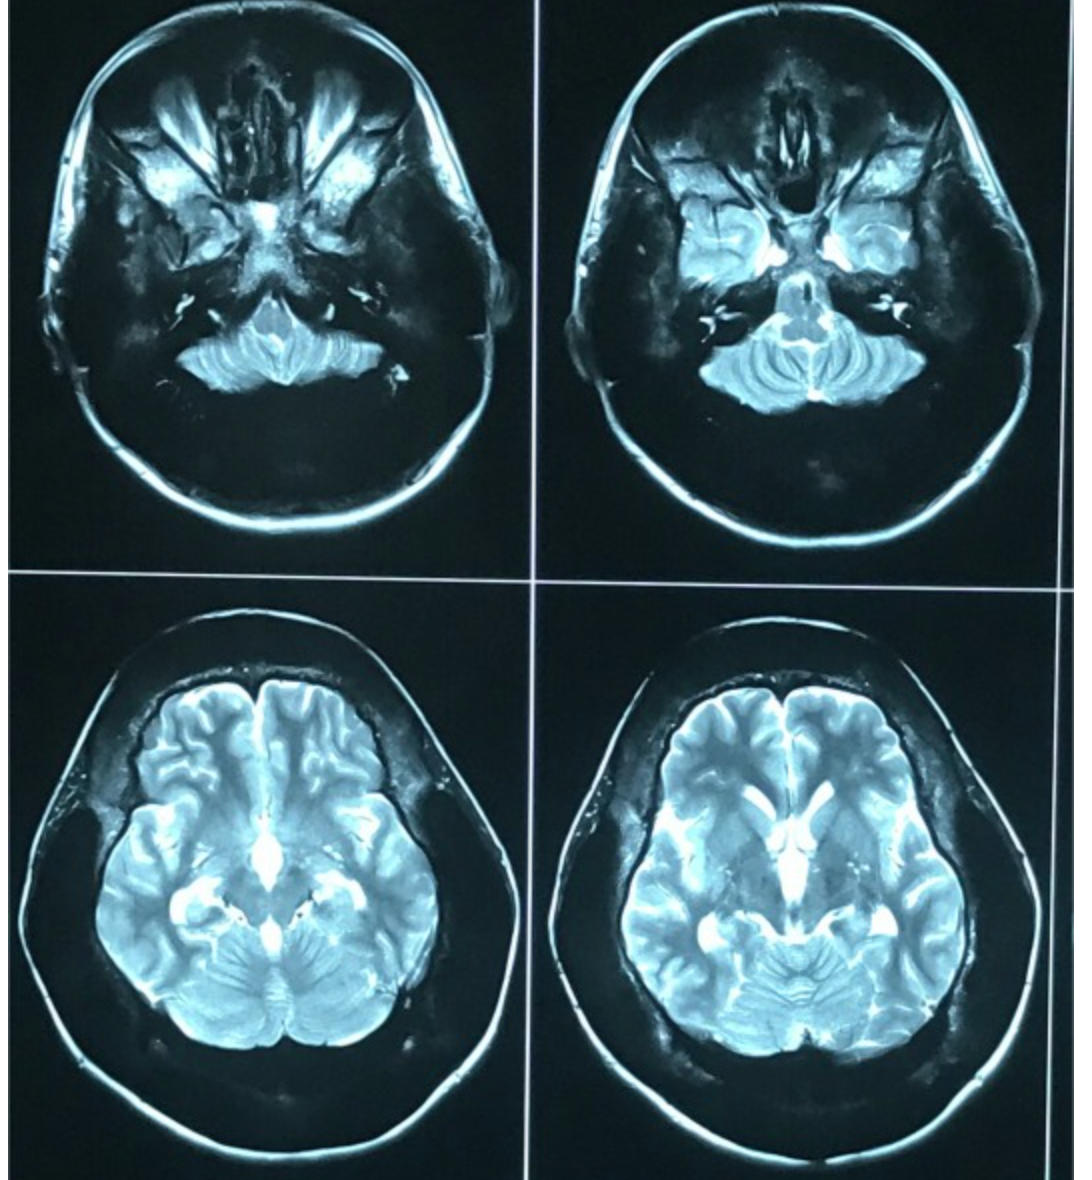

CT

High-density bone deposition within the membranous labyrinth:

mild disease: hazy increase in density within fluid spaces of the membranous labyrinth

moderate disease: focal areas of bony encroachment on fluid spaces of the membranous labyrinth

severe disease: membranous labyrinth completely obliterated by bone replacing fluid spaces

MRI

loss of normal high signal of fluid within the membranous labyrinth is seen on heavily T2 weighted images (as low signal intensity foci in the labyrinth)